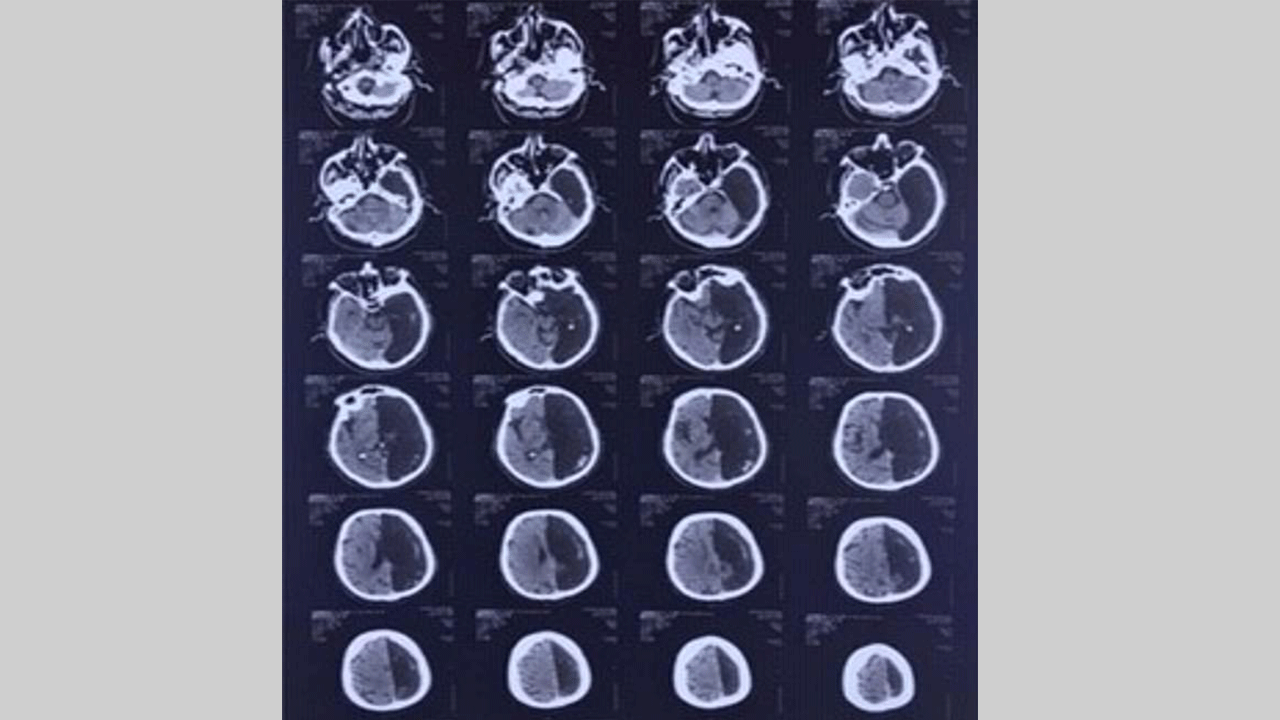

وقال أطباء أن الأشعة المقطعية التي أجريت للرجل بعد إسعافه نتيجة إصابته بجلطة في المخ أظهرت حفرة سوداء في الجزء الأيسر من دماغه.

كما أن نصف الكرة الأيمن الباقي من الدماغ قام طوال حياته بجميع وظائف المخ.